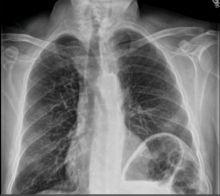

Symptomatic patients referred to the authors’ service with hemidiaphragmatic paralysis and/or eventration are investigated with chest x-ray, fluoroscopy (sniff-test), and spirometry. Only in patients where the etiology of the paralysis is unclear will an electromyography be ordered. Surgery is indicated in patients with dyspnea and loss of quality of life.

With the help of an endosuture device, the authors began the diaphragmatic plication from the cardiophrenic angle, anteriorly towards the lateral part of the chest wall. Single sutures were placed “by demand,” according to necessity. A second line of sutures was started at the costophrenic angle, again, towards the lateral chest wall. Progressively, the diaphragm elevation decreased and, with the sutures under traction anteriorly, the compression of the pericardial sac also decreased. Once the dome of the diaphragm was flattened, the lung regained volume and the pericardial sac was freed from compression. To better evaluate the result, during full re-expansion of the lung the authors confirmed that there was no contact between the lung and the diaphragm and that there was no pericardial compression. Finally, a 24 Fr chest drain was inserted. At 90 postoperative days, spirometry and chest x-ray were performed to evaluate lung function improvement.